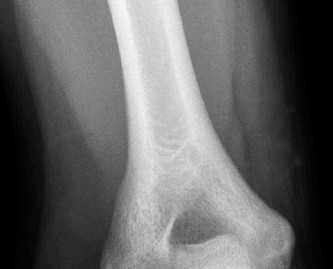

The patient undergoes resection arthroplasty with antibiotic cement spacer and a 6-week course of IV antibiotics. He returns to clinic 4 months later with improved pain, CRP <3, however, on examination he has a positive belly press sign and increased external rotation compared with the contralateral shoulder. Imaging is shown in Figure 2–57.

Figure 2–57

The correct answer is (D). The patient has completed his course of antibiotics and his spacer and is now an appropriate candidate for explanation of the cement spacer with revision shoulder arthroplasty, therefore Choices A and C are incorrect. The patient’s clinical examination findings point to rotator cuff tear (specifically subscapularis) which has occurred in the interval between his obtaining his initial total shoulder arthroplasty and his current examination. Therefore, total shoulder arthroplasty (Choice B) is contraindicated, and the patient should have a reverse total shoulder arthroplasty. Objectives: Did you learn...? Recognize the clinical presentation of a patient with infection after total shoulder arthroplasty?